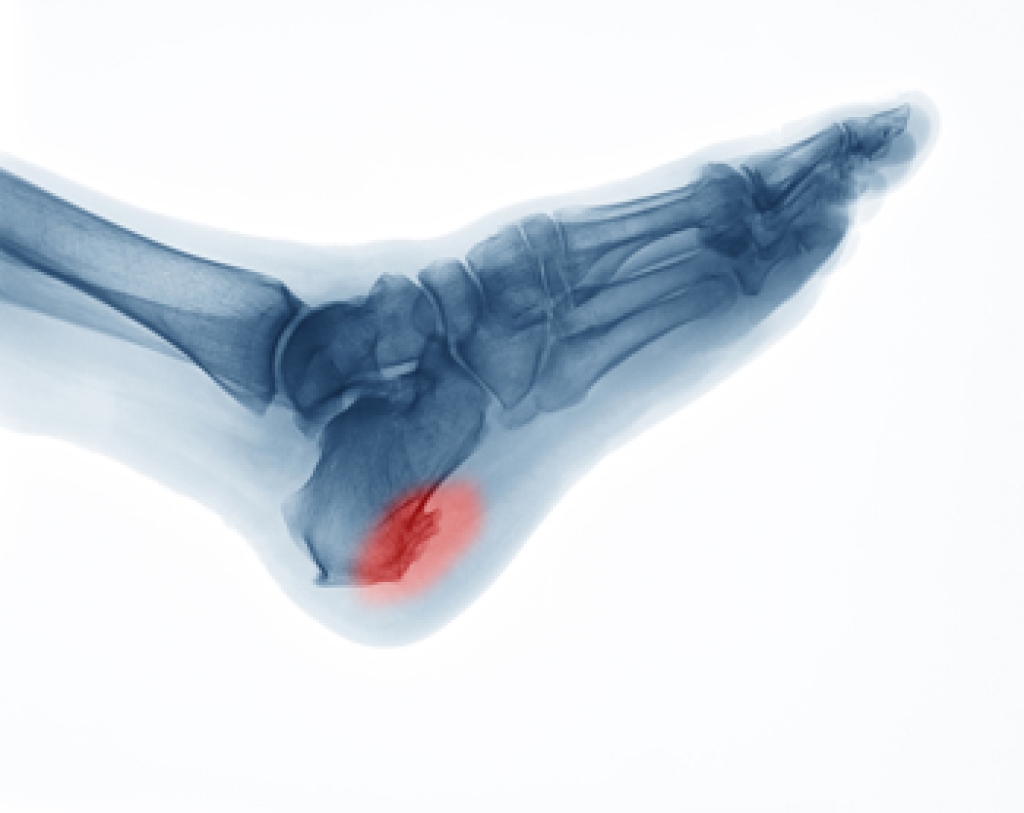

Gout is a form of arthritis that is characterized by sudden, severe attacks of pain, redness, and tenderness in the joints. The condition usually affects the joint at the base of the big toe. A gout attack can occur at any random time, such as the middle of the night while you are asleep.

- Intense Joint Pain - Usually around the large joint of your big toe, and it most severe within the first four to twelve hours

- Lingering Discomfort - Joint discomfort may last from a few days to a few weeks